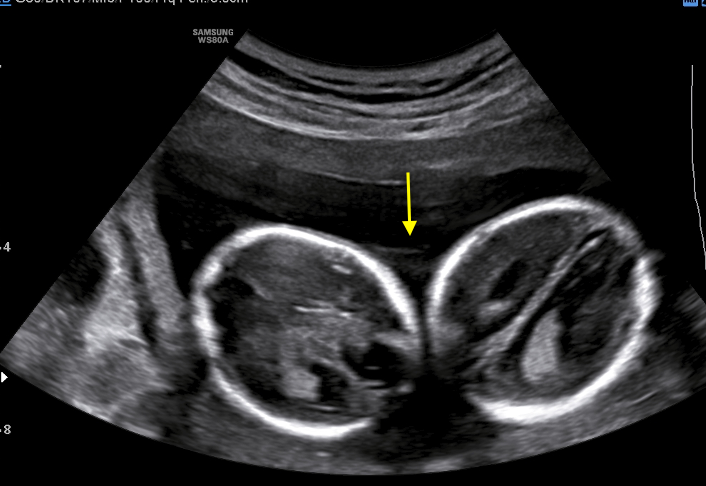

A healthy 39-year-old woman G4P3 was admitted to our high-risk pregnancy outpatient service due to a MC-DA twin pregnancy. Monochorionicity was suspected by the referring gynecologist during the dating ultrasound scan (US). The nuchal translucency US at the 12th week of gestation highlighted a “T” sign of the dividing membrane with a unique anterior placenta confirming a MC-DA twin pregnancy, as shown in Fig. 1. Soft markers for trisomy were found to be normal for both twins. The US performed during the 14th week of gestation showed the twins significantly closer to each-other standing on the same side of a free-floating thin membrane inserted on the placenta. This image raised the suspicion for a spontaneous septostomy (Fig. 2). The patient underwent amniocentesis as the combined serum screen showed an increased risk for Trisomy 21. US assisted invasive procedure did not detect the dividing membrane deposing for a PMM twin pregnancy following SS. A single sample of amniotic fluid was obtained and tested normal for fetal karyotype (46, XX). According to International Guidelines US imaging was performed every two weeks. Anomaly scan was normal and all subsequent Doppler US showed a normal twin growth and fetal wellbeing until the early third trimester [14, 15, 16]. The US performed at the 27th week of gestation showed a strict contiguity of the umbilical cords with a suspicion for cord entanglement on 3-dimensional (3D) US (Fig. 3A,B). The patient was hospitalized for close pregnancy surveillance. Fetal heart monitoring and US scan were daily performed. Steroids were administered for prevention of respiratory distress syndrome. The 29th week US scan highlighted a growth discordance ranging around 21% (symmetric growth at the 71° centile (estimated weight: 1328 gr) and at the 36° centile (estimated weight: 1043 gr) for Twin A and Twin B respectively). An episode of prolonged bradycardia was registered for Twin A. An emergency cesarean section was performed: two healthy girls were born (Twin A: weight 1360 gr, Apgar 4 and 7 at 1st and 5th minute respectively — Twin B: weight 1000 gr, Apgar 8 and 9 at 1st and 5th minute respectively). Cord entanglement was confirmed as shown in Fig. 4. The mother’s postoperative recovery was uneventful. Twins’ developmental follow-up at 12 months of age was normal.

Fig. 4.Intraoperative imaging of the cord entanglement during emergency cesarean section.